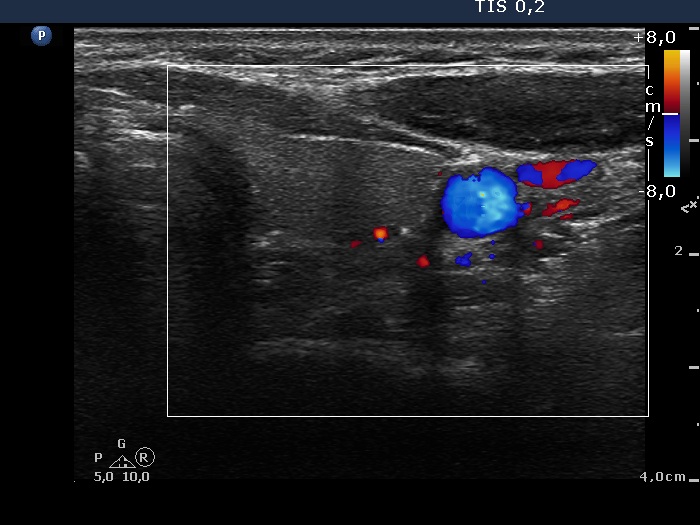

Intranodular hyperechogenic figures - case 624 (ultrasonographic picture 9)

Left lobe, trasnverse scan, color Doppler mode. The vascularization is not specific.